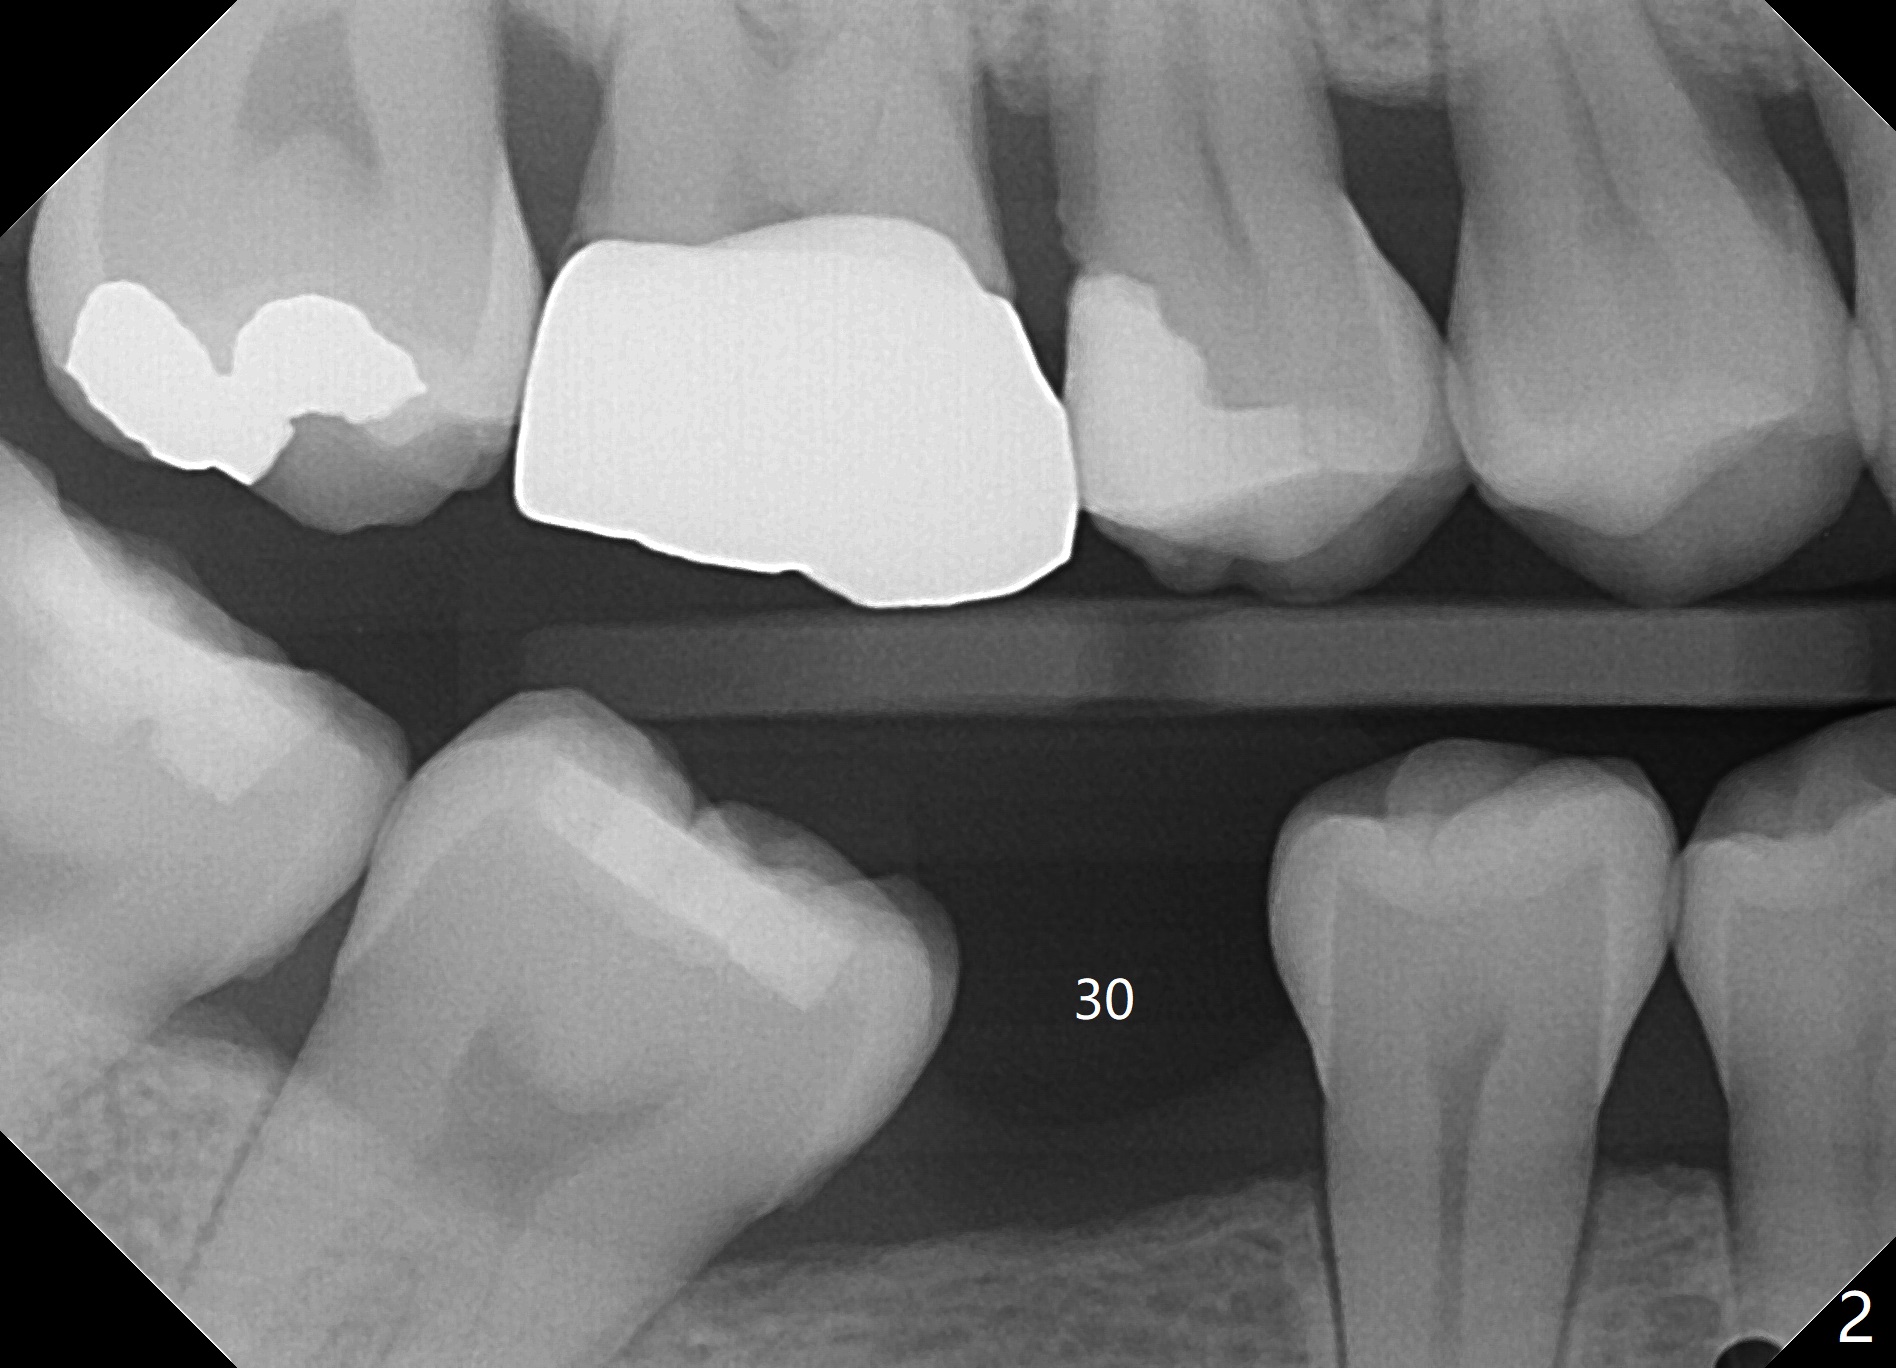

A 42-year-old woman requests extraction of the upper left 2nd primary molar with abscess (Fig.1,3,4). To avoid implants (for #30 as well in Fig.2) and improves cosmetics (anterior crowding), she chooses orthodontics with extraction of 2 more teeth in the other 2 quadrants. It seems necessary to have socket preservation so that the neighboring teeth have the bone to move to (Fig.5 without buccal plate collapse). In fact the coronal half of the buccal plate is resorbed. The bone regeneration is also important in case she changes her mind and ends up needing an implant. Return to Trajectory Xin Wei, DDS, PhD, MS 1st edition 05/17/2019, last revision 05/19/2019